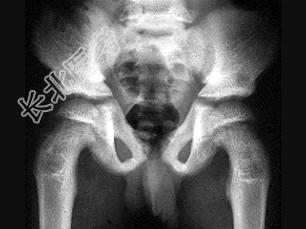

- 单项选择题男,6岁, 来自干旱地区,腰背疼痛四肢关节酸痛, 结合图像,最可能的诊断是 ( )

A、氟骨症

B、畸形性骨炎

C、石骨症

D、髋关节结核

E、甲状旁腺功能亢进